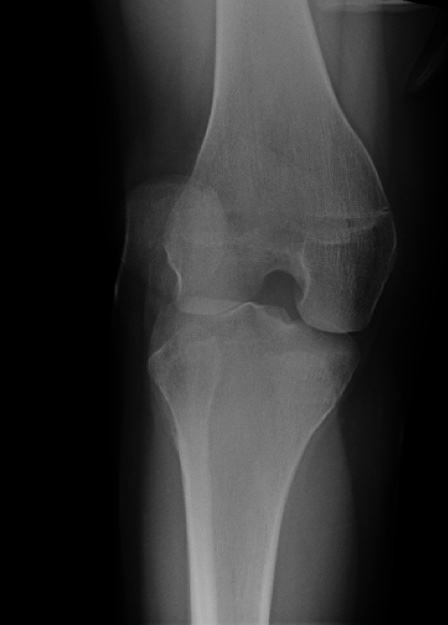

What’s the diagnosis? Gepost op 23 augustus 201823 augustus 2018 door netwerkvsseh What’s the diagnosis? @emdaily.cooperhealth.org Dit delen: Delen op X (Opent in een nieuw venster) X Share op Facebook (Opent in een nieuw venster) Facebook Delen op LinkedIn (Opent in een nieuw venster) LinkedIn E-mail een link naar een vriend (Opent in een nieuw venster) E-mail Afdrukken (Opent in een nieuw venster) Print Vind-ik-leuk Aan het laden... Gerelateerd